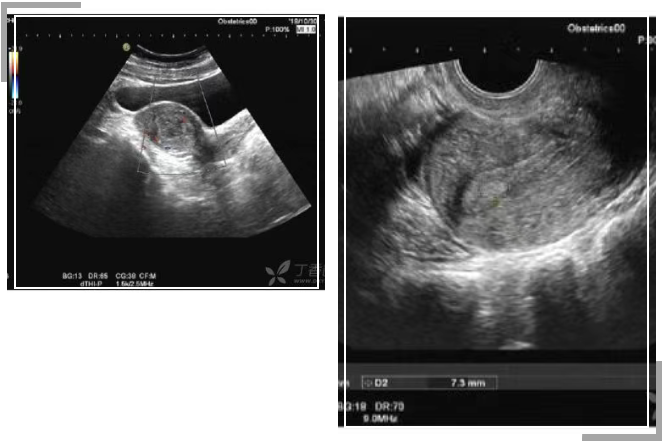

(1)B超下发现内膜不均

如果在B超检查后只是发现内膜不均,并未明确有息肉和粘连的迹象,也没有其他症状,这种情况下,不建议进行宫腔镜手术,但是可以考虑先做个宫腔镜检查,这样既可以避免可能的问题,又避免过度手术的风险。

(B 超结果均示:子宫内膜回声不均)